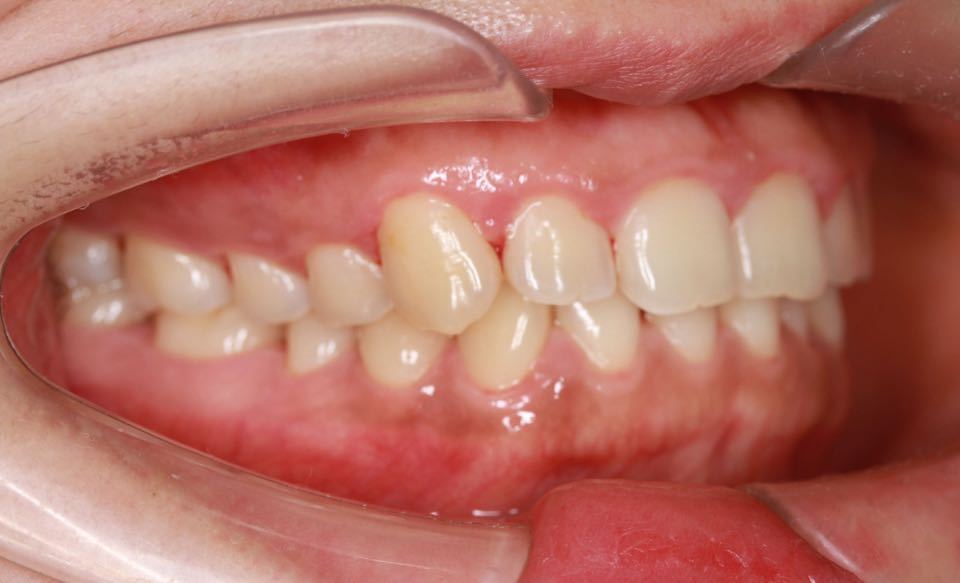

矫正前口内照:

侧面观:软组织面型正常,直面型。

口内:恒牙列,牙列拥挤(中度)。上下颌牙弓呈方圆型。左右对称。右侧磨牙近中性关系,左侧磨牙近中关系,右侧尖牙远中关系,左侧尖牙远牙中性关系。上颌中线偏右2mm,下中性居中。